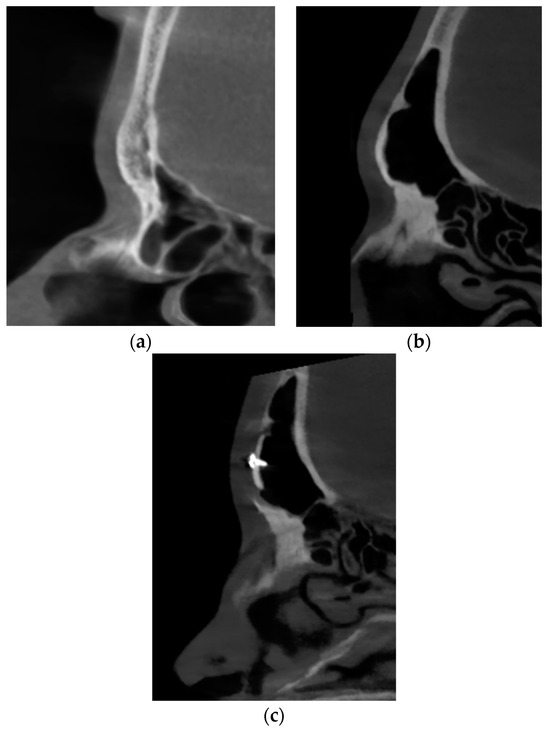

Forehead reduction in transgender facial surgery is commonly discussed in various publications. We do, however, prefer the classic approach described by Ousterhout. Type 3 surgery (reconstruction) was necessary in 75% of the cases. Surprisingly, revision cases were previously wrongly qualified patients for Type 1 reduction (bone burr). This was probably due to common undercorrection of the forehead, where Type 3 was really needed, but an unexperienced surgeon chose to burr down the cortical bone in a way not to open the sinus, leaving a thin wall. This was a frequently reported mistake, as Type 1 is only justified by an underdeveloped or lack of frontal sinus (Figure 4) [1]. In our cohort, only 10% of cases were Type 1 reduction, which generally agrees with the statistics published in other studies (Figure 5) [1,7,14,15].

Figure 5. Sagittal sections of the frontal sinuses of two different patients who attended for the feminization of the upper third (not revision cases). (a) agenesis of the frontal sinus, which allowed for Type 1 forehead reduction. (b) large pneumatic frontal sinus, which required resection, remodeling, 5 mm setback, and osteosynthesis stabilization (Type 3). (c) the same sinus after feminization.